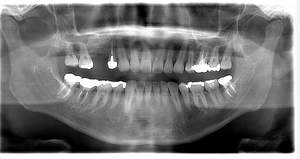

レントゲン写真

- Before

- After

| 年齢 | 60代・男性 |

|---|---|

| 主訴 | 右下6番7番 |

| 治療内容 | インプラント |

| 治療費 | インプラント診断料 55,000円 インプラント埋入料 165,000円×2 サージカルガイド 66,000円 2次OPE 22,000円×2 インプラント仮歯 55,000×2 インプラント上部構造 187,000×2 静脈内鎮静麻酔 77,000円 合計 1,056,000円 (2024年1月現在) |

| 治療期間 | 7ヶ月 |

| リスク・副作用 | リスク・副作用 |

| 治療方針 | 元々右下6番7番が欠損している状態でした。 前歯部にブリッジが入っているため長持ちさせるには咬合力を分散させればブリッジがもつ可能性があるため、欠損部のインプラントを行いました。 |

| 特記事項 | インプラントは人工物なので虫歯になることはありませんが、歯周病(インプラント周囲炎)にはなります。 インプラントを長持ちさせるには、毎日の歯磨きと合わせて、3~6ヶ月ごとの定期検診でのクリーニングが大切です。 |

| 担当者所見 | 歯を失ったまま放置してしまうと、周囲の歯に負担がかかるため、お口の中全体のバランスが崩れます。 インプラントは、骨に人工の歯根を埋め、被せ物を被せる治療法です。 外科的な手術が必要ですが、健康な歯を削ることなく、天然の歯と同じようにかめるようになります。 |